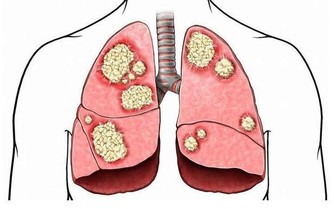

5. 你莫名其妙地減重

體重迅速下降且伴隨著打嗝,是腸道阻塞的標誌。如果你本來不打算減肥,體重卻在快速下降,則可能意味著你的身體沒有正確地消化你所吃的食物,醫生可能會檢查你是否患有如腸易激綜合徵、食物過敏或克羅恩病在內的疾病。另外,打嗝與體重下降同時出現,也很可能是胃癌的徵兆。